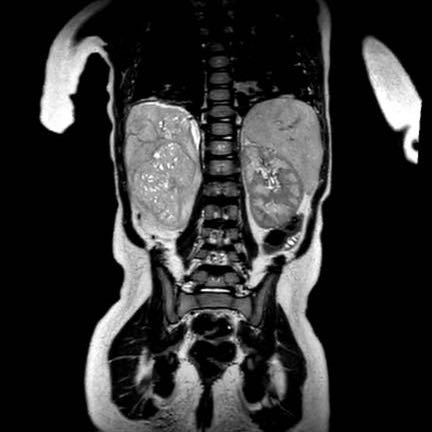

Trên MRI, nephroblastomatosis được quan sát rõ nhất trên các chuỗi xung sau tiêm thuốc tương phản từ và chuỗi xung khuếch tán (DWI).

Hình ảnh

Các hình ảnh MRI của cùng bệnh nhân cho thấy tình trạng giảm tưới máu của mô bệnh lý và hạn chế khuếch tán mạnh với giá trị ADC thấp.

Bệnh nhân được điều trị hóa trị liệu tiền phẫu, sau đó khối u ở bên trái được cắt bỏ qua phẫu thuật cắt thận bán phần. Nephroblastomatosis lan tỏa được điều trị bằng phác đồ hóa trị AV (Actinomycin D và Vincristin) hàng tháng trong một năm.